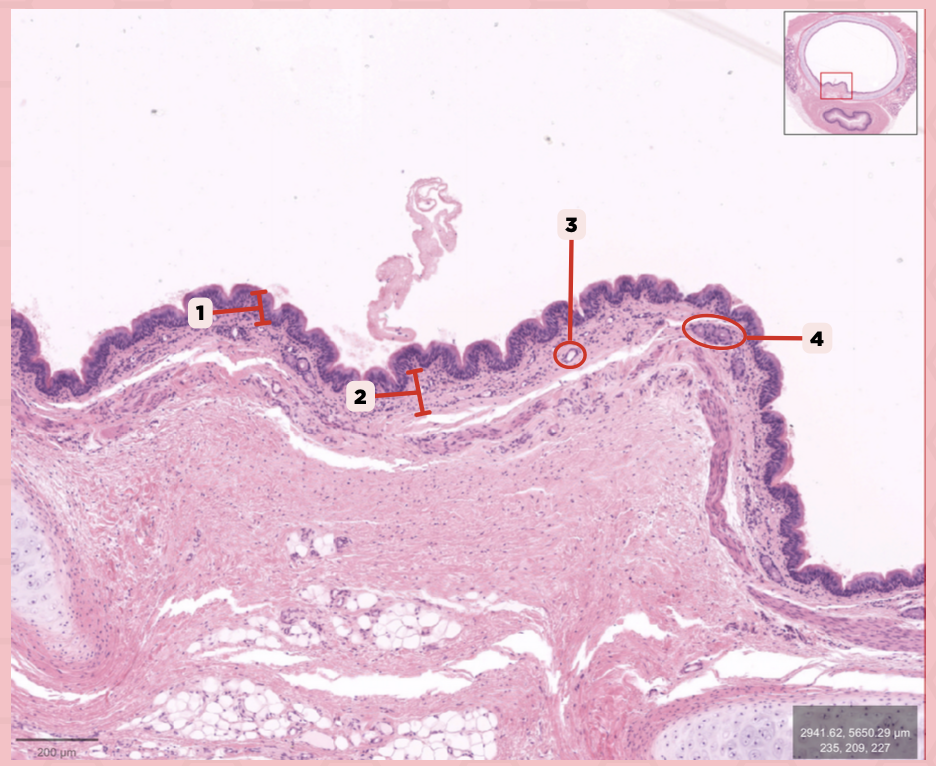

Nasal Cavity

What are the spaces found immediately lateral to #2?

Nasal Turbinates (conchae)

Identify the structure labeled as 1.

Nasal septum

Identify the structure labeled as 2.

Nasal cavity

Identify the structure labeled as 3.

Hard palate

Identify the structure labeled as 4.

Mucosal Associated Lymphoid Tissue (MALT)

What time of lymphocyte is numerous in the nasal cavity?